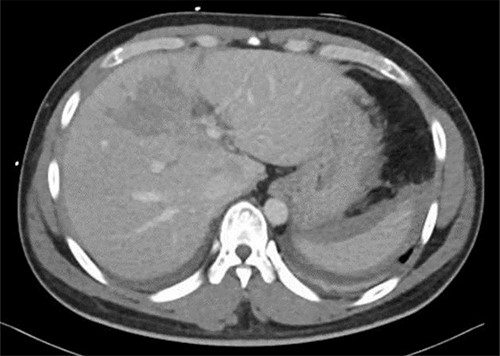

After 1 week of embolization, a follow-up CT scan detected thrombosis of the lateral segmental branch of the left portal vein. Prophylaxis dose of heparin was increased to the therapeutic range and, a week later, duplex US examination was performed, which documented the resolution of this thrombosis. The patient was transferred to the rehabilitation care on daily oral aspirin. A repeat CT scan was done after 1 month in which no pseudoaneurysm was seen, with normal flow in the hepatic arteries and portal vein (Fig. 7). During the following 2 months, the patient remained asymptomatic and was discharged home without complications.

Repeated CT scan of the abdomen after 4 weeks revealed partial healing of the liver injury with disappearance of the pseudoaneurysm.